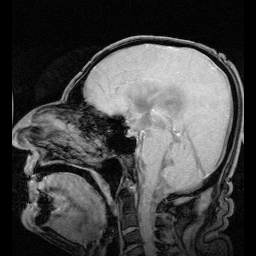

1. 뇌척수액의 구조

1) 중추신경계를 둘러싸고 있는 뇌척수막(연막. 지주막. 경막) 내부에서 만들어지는 액체입니다.

3) CST치유로 인한 두개골의 이완

○척수액활동이 어떤 여러 가지 이유로 원활하지 못하거나 막혔다면 중추신경계의 이상으로 온다. 그럴 때 CST요법은 두개골의 이완을 도와준다.

두개골은 22개의 뼈로 되어있는데 그 뼈들 사이를 연결해 주는 봉합면이 있다. 그 봉합면들이 톱니바퀴모양으로 되어있으며 그 면들이 조금씩 움직이면서 호흡을 하고 척수액을 도는데 큰 역할을 한다. 그래서 CST로 두개골 봉합면을 잘 이완을 시켜주면 CST치유효과는 배가 되고 특히 척수액문제로 대표되는 알츠하이머. 뇌졸중. 인지장애. 집중력장애. 건망증. 발달장애. 성장애. ADHA대상포진등의 면역력과 관련되는 여러 문제들을 해결하는데 큰 도움이 된다.